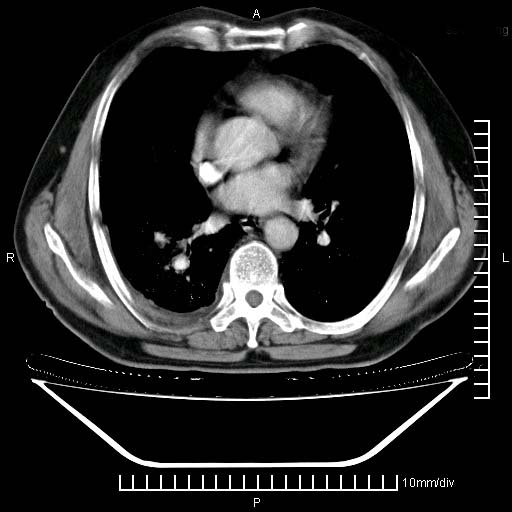

既往肺结核,近10几天,咳嗽,咳痰,右侧胸痛,疼痛较明显,右上肺斑块考虑结核灶胸膜粘连,增强,可惜动脉期没有定好,未见强化,可延迟4分后又见较明显强化,中心见低密度影,如果说结核是边缘强化,可这个灶强化的面积挺大的,让人很挠头。

强化的组织可能是膨胀不全的肺组织或炎性肉芽组织。

1)两肺继发性肺结核。2)右侧胸膜增厚+少量胸腔积液。